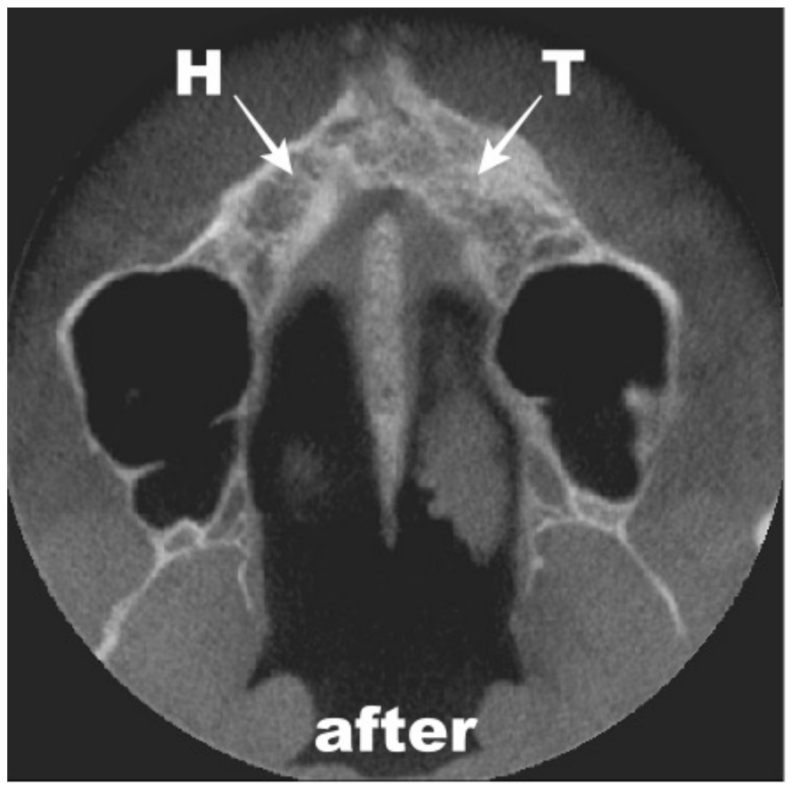

4. Results